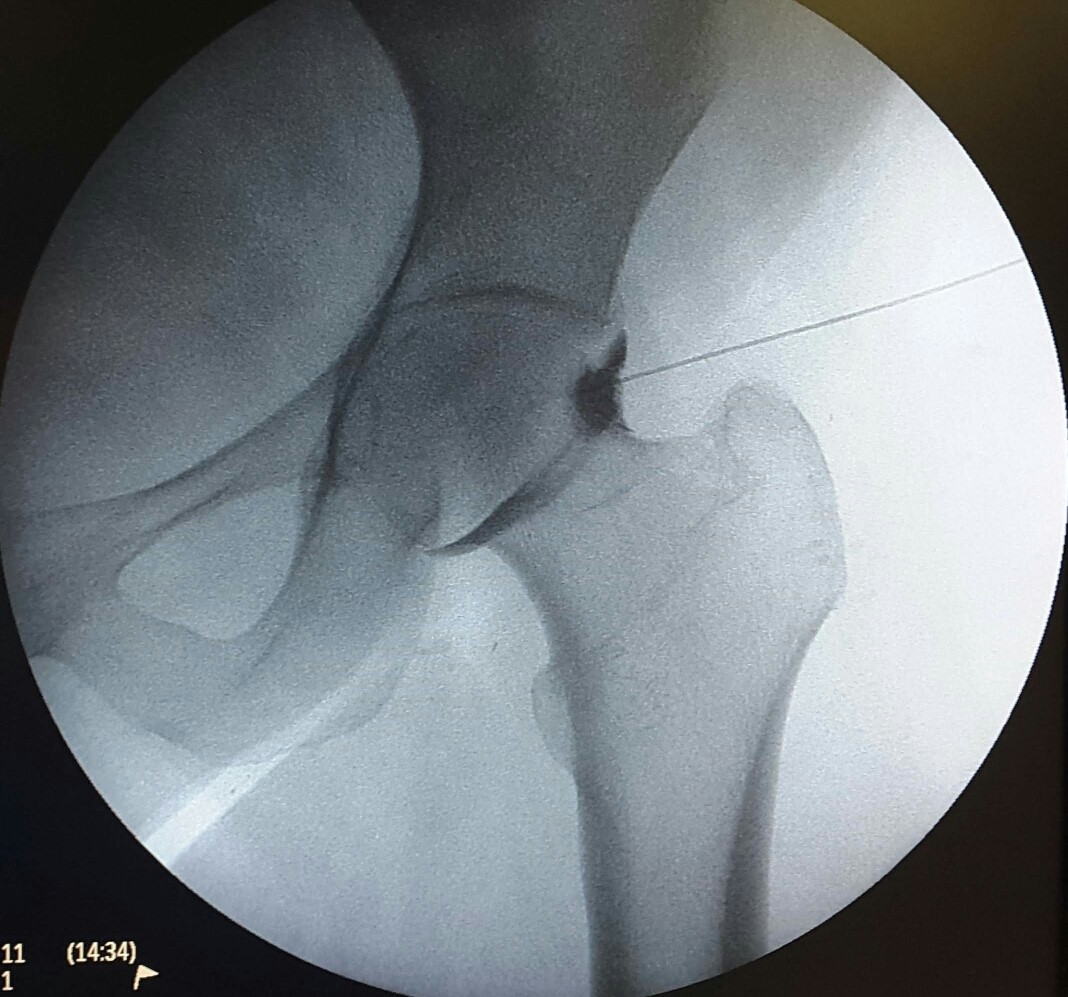

Η ενδαρθρική έγχυση του ισχίου αποτελεί μία θεραπευτική αλλά και διαγνωστική επιλογή

σε ασθενείς που πάσχουν από χρόνιο πόνο στο ισχίο που δεν υποχωρεί με άλλους

συντηρητικούς τρόπους.